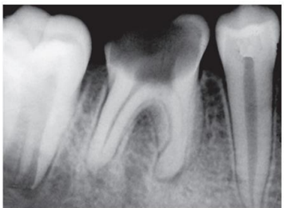

Observe a imagem abaixo, onde o elemento

dentário em questão apresenta-se com Necrose

Pulpar com Periodontite Apical Aguda.

Marque a alternativa que descreve corretamente as características da necrose pulpar com periodontite apical aguda.